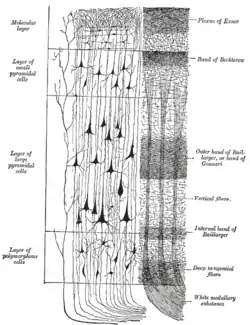

Cerebral cortex. To the left, the groups of cells; to the right, the systems of fibers. Quite to the left of the figure a sensory nerve fiber is shown. | |